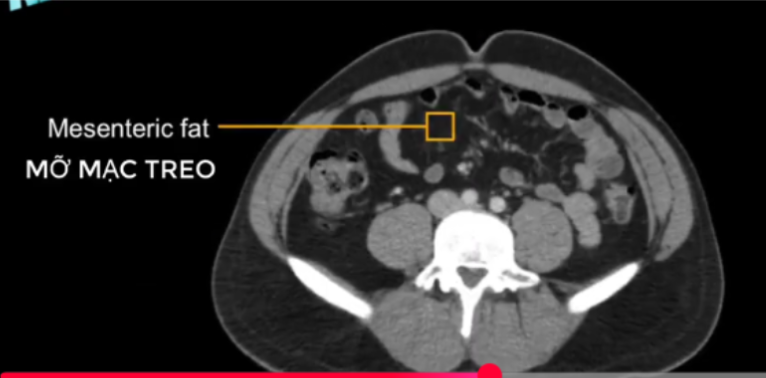

cq trong hình ?